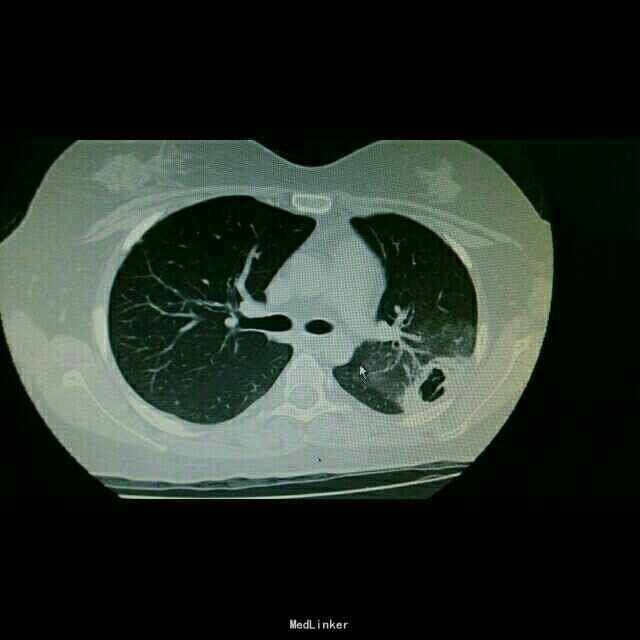

查体:双肺湿罗音,余无特殊。 辅查:9.10胸部CT双肺炎症。10.2原炎症部位出现空洞。10,21原炎症部位好转,空洞无明显变化。

诊断:肺曲霉病。 治疗:开始予以伏立康唑治疗,仍有发热,后予以两性霉素*B治疗。

随访:继续予以两性霉素B治疗,总量用至1g。 讨论:对于大剂量激素治疗,容易导致真菌感染。而所有抗真菌药物都是以两性霉素B为对照研究抗菌能力的。用要过程密切注意患者肝肾功能的情况。